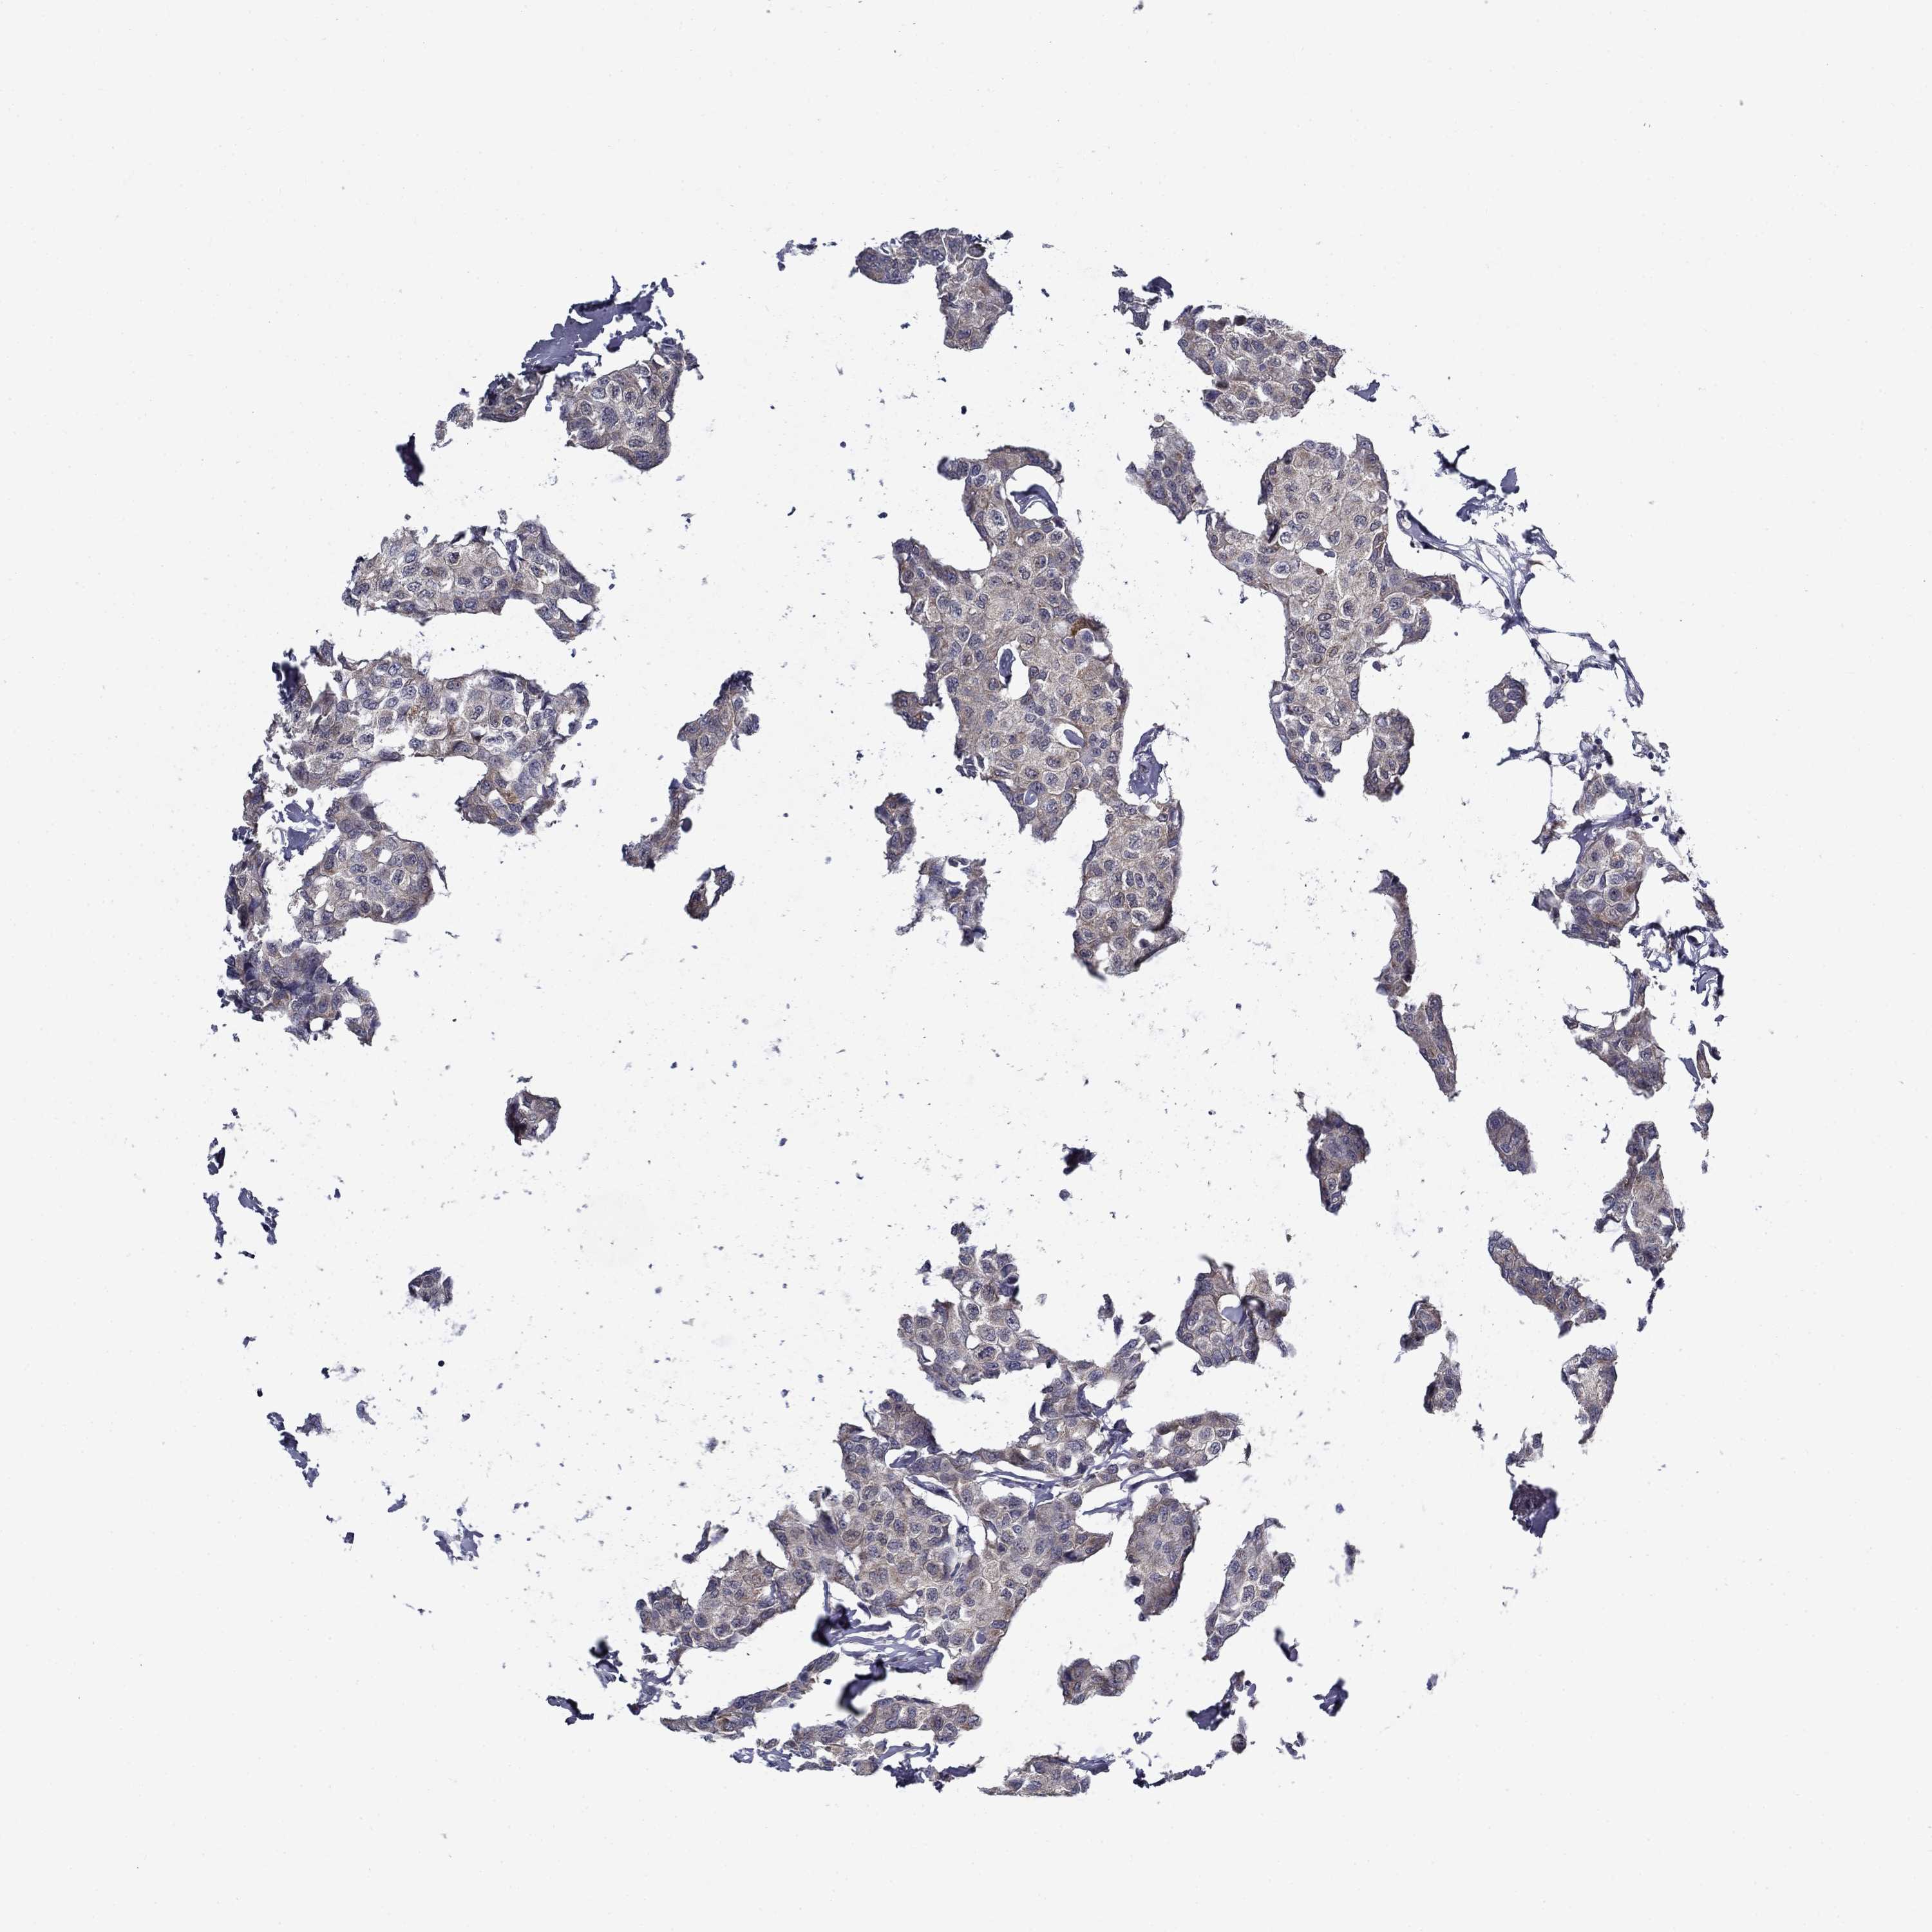

BRCA TCGA BRCA VALIDATION PROTEIN EXPRESSION